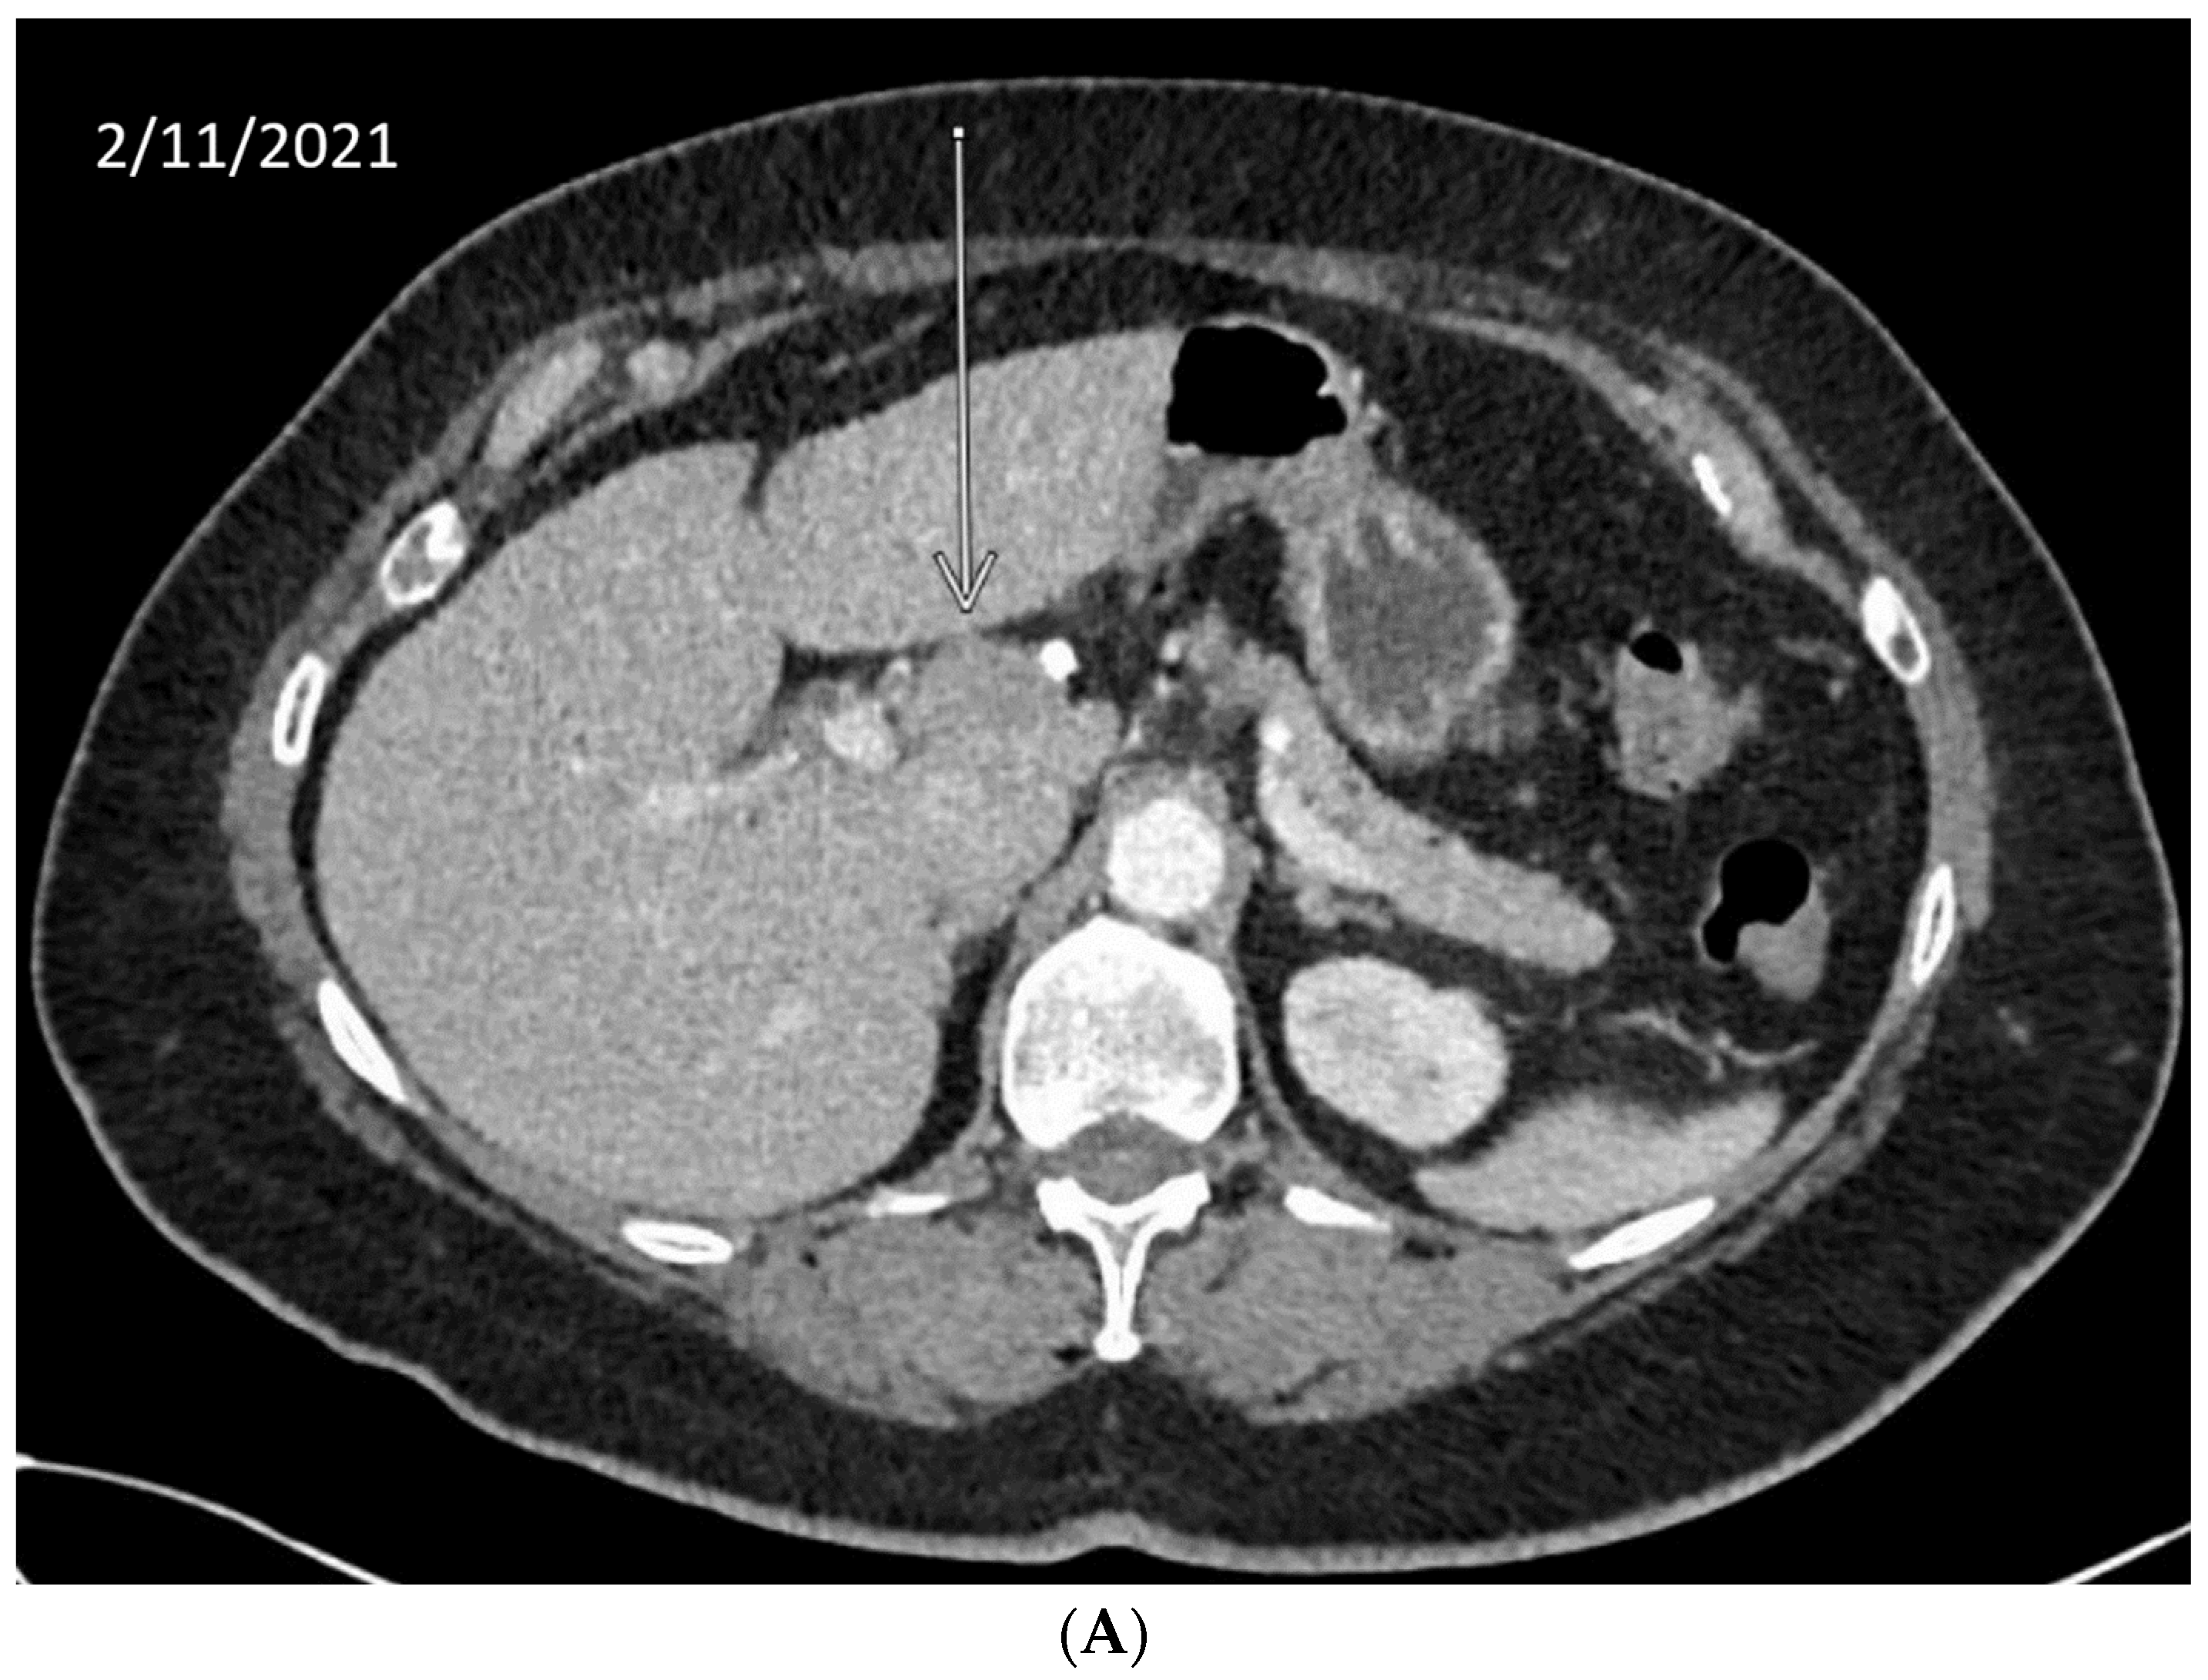

10. Anecdotal Case of RAD51 Mutation in CCA

| BAP1 | Involved in chromatin modulation and transcriptional regulation. It localizes in the endoplasmic reticulum, where it binds, deubiquitylates, and stabilizes IP3R3, modulating calcium release from the endoplasmic reticulum and apoptosis [44]. In HR, it regulates and recruits key downstream effectors, including p53, BRCA1, and RAD51. It is phosphorylated by ATM [45]. | 7.4% | Case report: Patient with refractory metastatic CCA with novel BAP1 mutation (splice site c.581-17_585del22) had a good, prolonged response to olaparib (>11 months) [46]. Clinical: Rucaparib in patients with BAP1-deficient (by immunostaining) or BRCA1-deficient recurrent mesothelioma showed early signs of efficacy (disease control rate at 12 weeks was 58%) [47]. |